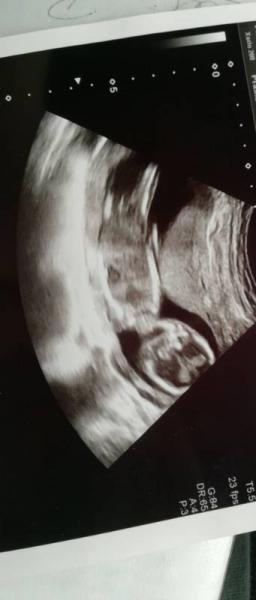

Wir hatten heute auch regulären Ultraschall Termin. Und juhuuu die plazenta ist schon etwas hoch gewandert das heißt sie ist bald stabil und nicht mehr tiefsitzend. Zwerg geht es auch gut

haben ein sehr lustiges Bild bekommen nur beim outing war ich enttäuscht. Er hat gar nicht wirklich geschaut meinte wichtiger wäre die plazenta etc. Naja in 3 Wochen hab ich wieder Termin. Vielleicht ja dann

Bild ist ja wirklich süss herrlich meine war heute sehr am turnen jede position gezeigt

Das freut mich das alles gut ist. Auf dem Bild sieht es für mich irgendwie aus wie ein Bub. Man könnte sich einbilden das da was zwischen den Beinen ist.

Dachte ich auch schon.. Aber ich weiß nicht ob es "einer" ist . Hab gedacht wenn es so deutlich gewesen wäre hätte der fa doch sagen können...

Aber ich finde auch das es so aussieht

aber das Bild ist interessant! das Gerät ist ja sehr genau, da sieht man ja die Gehirnhälften usw.

Also ich finde auf den Bild sieht man eindeutig das es ein Junge ist. Ich finde offensichtlicher geht es garnicht

Bei meinen Sohn sah es genauso aus

Ich weiß gar nicht wie groß steht auch nichts auf dem Bild. Alles entspricht 15+2. Ach es ist mir eigentlich so egal was es wird. Dieses kleine menschlein hat sich uns ausgesucht und es hat mehr als einmal bewiesen das es gerne bei uns bleiben will und hat allen Blutungen und Hindernissen getrotzt.

Sieht auf dem bild aus wie Junge

Ich sehe da seeeeehr viel Stoff zwischen den Beinen :D Aber schön dass alles in Ordnung ist! Ach, ich liebe die Vorsorgetermine. Ich weiß gar nicht wie die Frauen das in den Niederlanden oder Skandinavien aushalten, wenn es stimmt was ich gehört habe. Da gibt es dieses breite Vorsorgesystem wohl nicht.

Ich sehe ein zipfelchen